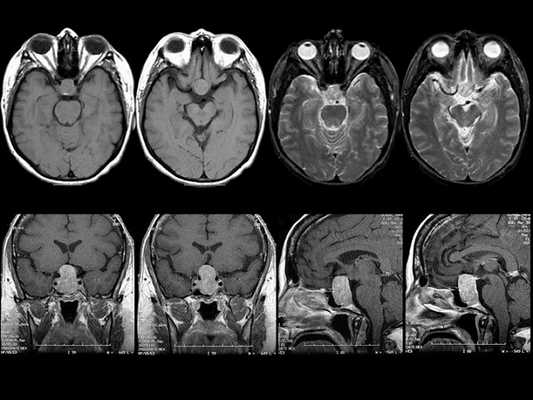

МРТ гипофиза при краниофарингиоме: сканы в разных проекциях

Магнитно-резонансная томография - один из высокоинформативных способов инструментальной диагностики. Исследование показывает мельчайшие изменения в структуре органов, предположительный характер патологии, взаимоотношение с близлежащими структурами. Скульптурирование многоплоскостных изображений во время МР-сканирования подразумевает использование принципа ядерно-магнитного резонанса, но не рентгеновских лучей. Атомы водорода в клетках воды, попав в поле, генерируемое аппаратом, начинают перестраиваться, при обретении привычного положения выделяется определенное количество энергии, которое фиксируют датчики, а обрабатывает компьютерная программа. Какого-либо вредоносного воздействия на организм во время диагностической процедуры нет, при условии отсутствия в теле металлических составляющих. Врач получает возможность рассматривать патологический очаг в любой плоскости, что невозможно при обычной рентгенографии или КТ.